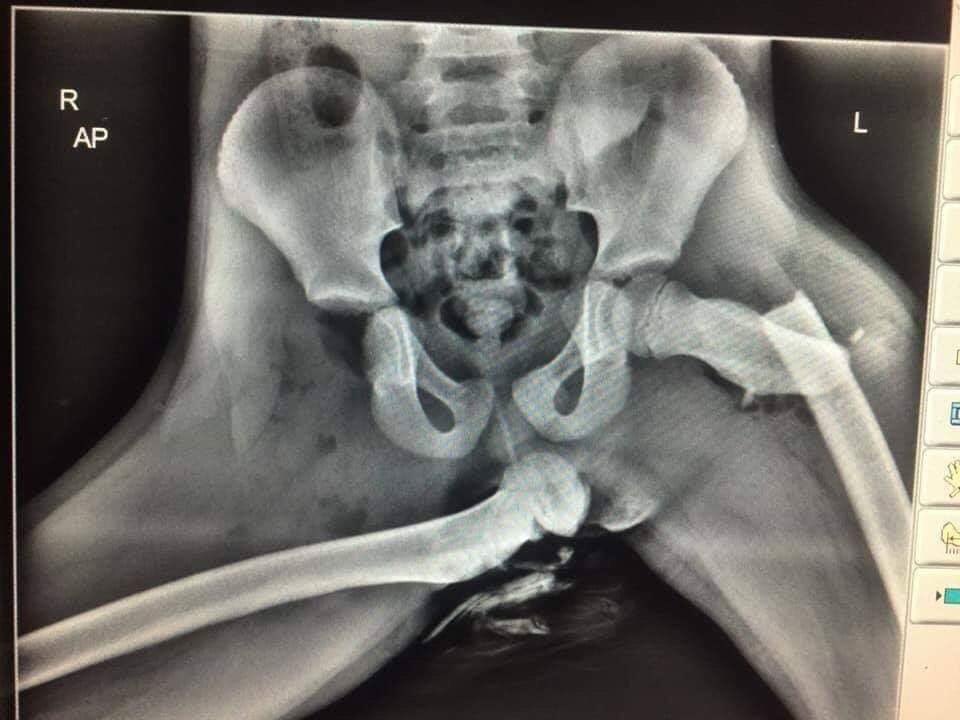

À l’approche de l’été, il est toujours bon de rappeler qu’une simple collision en voiture, peut déclencher un airbag à une vitesse allant entre 200 et 300 km/h qui dans cette position peut vous briser le bassin

tony_rdn's tweet image. À l’approche de l’été, il est toujours bon de rappeler qu’une simple collision en voiture, peut déclencher un airbag à une vitesse allant entre 200 et 300 km/h qui dans cette position peut vous briser le bassin